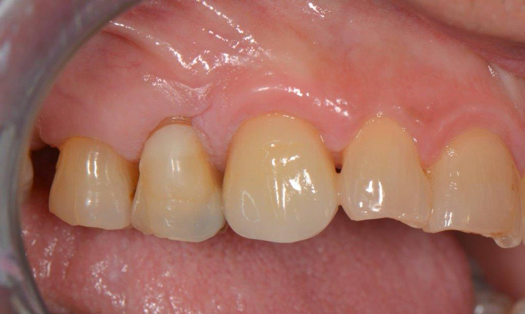

Fig 6. After splint removal (12 weeks postoperatively).

Figure 6

Figure 3 through Figure 5 show the fitting of a one-piece multiple splint using a light-cured acrylic, along with flowable composite to adhere the splint to the three ceramic dental implants. The splint was to remain out of occlusion, without any occlusal forces for the 12-week osseointegration period. The patient was instructed to chew on the other side of her mouth for the 12 weeks before returning to the dental practice for simple removal of the splint. Removal of the splint revealed optimum results. The soft tissues were pink, with keratinized gingival margins completely surrounding the ceramic implants and consistent with what most dentists observe with the periodontium around periodontally healthy natural teeth (Figure 6 and Figure 7).